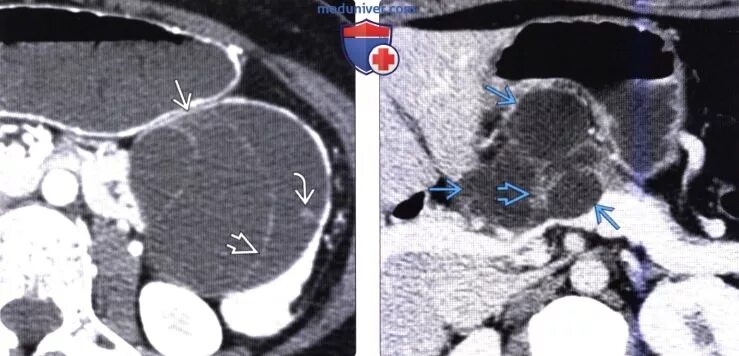

Диффузные изменения киста поджелудочной железы